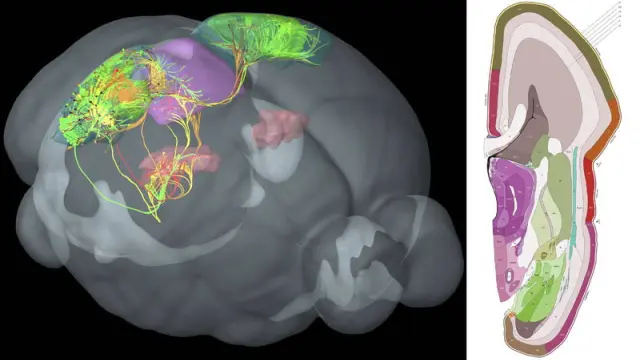

La amígdala es una de las partes más profundas del cerebro, que, desde el punto de vista evolutivo, cuenta con estructuras subcorticales antiguas, como, además de la amígdala, el hipocampo, y otras posteriores como la corteza, la parte externa que cubre los dos hemisferios.

"El circuito que llega a la amígdala es como la calzada de una ciudad romana. Sobre ella han pasado muchas otras civilizaciones pero todavía sigue en uso", cuenta a EFE Bryan Strange, director del Laboratorio de Neurociencia Clínica del Centro de Tecnología Biomédica de la Universidad Politécnica de Madrid (CTB-UPM) y autor principal del estudio.

Esta parte del cerebro es la encargada de procesar el miedo y la mayor parte de las emociones de carga negativa como la ira.

Este atajo neuronal es un circuito neuronal formado por células del tipo 'magnocelular', las más rápidas llevando información al cerebro, incluso aunque sean de baja frecuencia, mala calidad o borrosas, explica Strange.